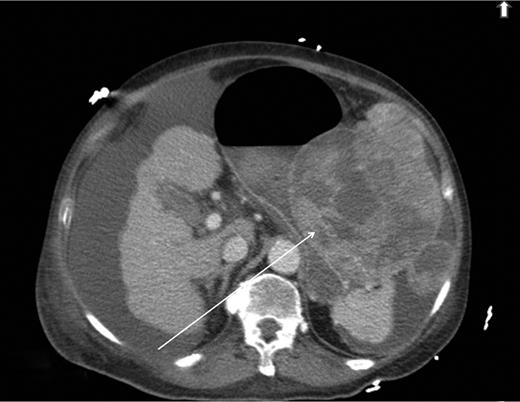

During the second day of admission, the patient passed out large amounts of melena and had an episode of haematemesis. She also developed tacchycardia with heart rate increasing to 110–120 b.p.m. Repeat blood investigations showed that haemoglobin had fallen from 6.8 to 5.3 g/dl despite blood transfusion. An emergency oesophagogastroduodenoscopy was performed. Findings were that of grade 1 oesophageal varices with no features of variceal bleed. There was a large clot in the fundus and cardia of the stomach. After attempted removal of the blood clots with flushing, the patient developed torrential bleeding necessitating intubation for airway protection. The bleeding eventually ceased spontaneously and the source of bleeding was identified to be originating from a large ulcer crater in the greater curve with an overlying clot (Fig. 1). Endoscopic ultrasound was performed which showed a 10 cm mass lesion abutting the stomach wall and extending into the peritoneal cavity (Fig. 2). The preliminary impression was that of a bleeding GI stromal tumour and care was transferred to the surgical team for consideration of surgical intervention.

Endoscopic ultrasound showing lesion abutting stomach wall extending into peritoneal cavity.

Diagnosis of upper GI invasion by HCC causing haemorrhage is difficult and can be easily missed. Radiological imaging may show a bulky HCC invading into the stomach or duodenum, but there have been numerous cases of upper GI tract involvement by HCC which were not demonstrated on imaging [4–6]. Hence, the absence of typical features of tumour invasion in imaging studies does not exclude the pathology. Compared with imaging, endoscopy may better visualize these lesions but HCC invasion of upper GI tract can adopt a myriad of appearances ranging from an ulcerative bleeding mass to a polypoidal or submucosal mass with or without features of extrinsic compression [5]. Thus, it requires a combination of imaging, suggestive endoscopic findings and a high index of suspicion before a diagnosis of HCC invasion causing upper GI haemorrhage can be confidently made. Endoscopic ultrasound may be a useful adjunct as demonstrated in our case. It identified the lesion to be originating from the peritoneal cavity which on hindsight should have led us to consider HCC invading into the stomach as a differential diagnosis in this patient with long-standing liver cirrhosis.